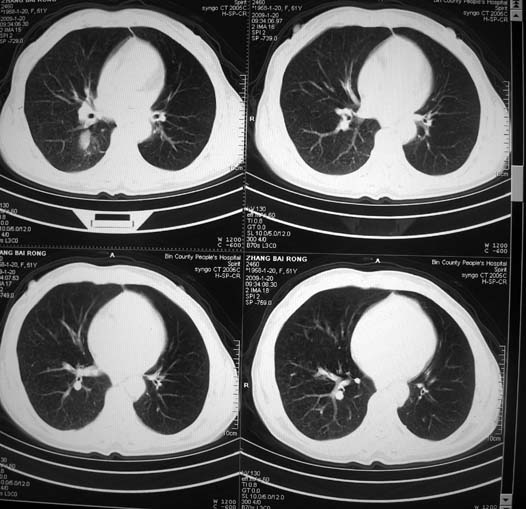

以下是引用zsl6918在2009-1-20 17:30:00的发言:[br]支持右肺下叶背段周围型肺癌,隆突下淋巴结肿大

以下是引用宇宙ct在2009-1-20 16:28:00的发言:[br]周围性肺癌\\纵隔淋巴转移

以下是引用sos.la在2009-1-20 18:01:00的发言:[br]实质性密度均匀肿块.边界清晰,浅分叶.无明显毛刺征,离胸膜近却无胸膜凹陷征,发生在段及段以下支气管,病灶直径远远超过此位置支气管管径而无阻塞征象,7#淋巴结肿大,病理是小细胞未分化癌(局限期)可能性最大.